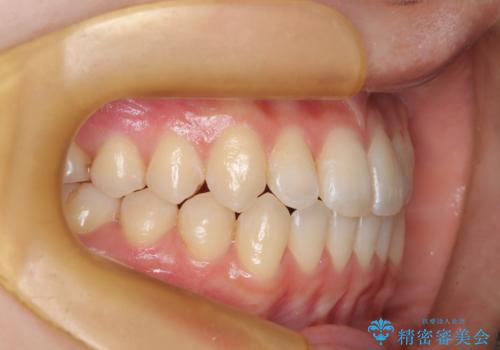

前歯のガタつき、下顎の前突感を治したい インビザライン矯正例

- 治療計画

- 学生時代に矯正治療を経験されていましたが、その後の後戻りによる前歯の叢生・下顎の前突感を主訴に来院されました。叢生や口元の突出感が軽度であった為、非抜歯にて側方拡大やIPRを組み込んでインビザラインにて治療を計画しました。前歯部にクロスバイトがあり、治療途中に上顎前歯が下顎前歯を乗り越えなければならない時期もありましたが、患者様の協力的なマウスピース装着もあり、良好な配列を達成しました。上下左右の親知らずは、当院にて矯正開始前に抜歯しました。